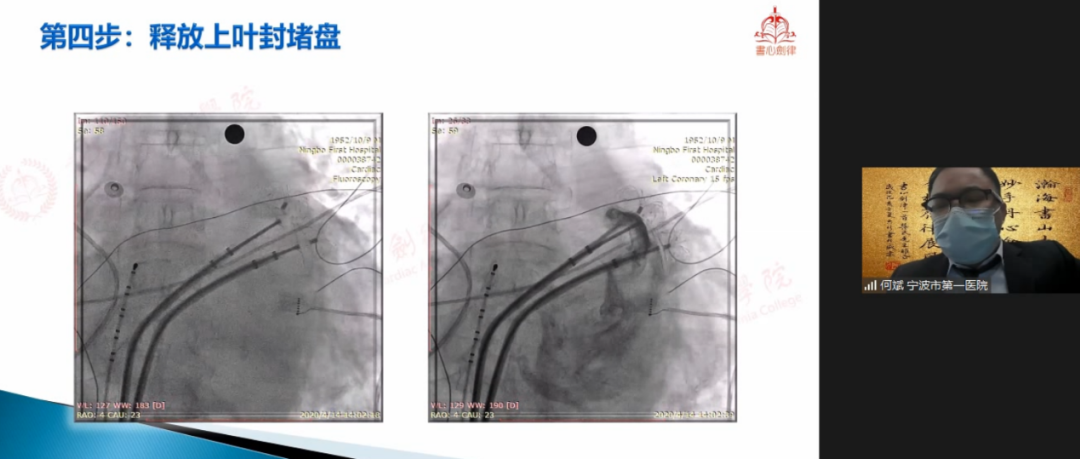

何斌教授

宁波市第一医院何斌教授在会议中与专家们共享LAmbre™双伞封堵大心耳经验。该病例为81岁男性,被诊断为持续性心房颤动,CHA2DS2-VASc评分6分、HAS-BLED评分4分,既往有左心耳血栓、卒中病史。抗凝治疗6月后,TEE下未见心耳血栓。术中DSA造影提示患者为双早分叶心耳,上叶梳状肌发达,下叶较为光滑,心耳口部直径45mm。已有临床实例表明,LAmbre™行双伞封堵具有可行性,结合患者情况、家属意愿及心耳形态等多种因素,何斌教授最终拟定为患者行双伞封堵策略。何斌教授首先行两次房间隔穿刺并再次造影确认心耳形态及大小,测量得上叶锚定区21.6mm,下叶锚定区19.4mm,随后选用LAmbre™2228封堵器先行封堵下叶,牵拉测试稳定后,选择LAmbre™2430封堵器封堵心耳上叶。最终,双伞牵拉测试稳定,TEE多角度评估双伞形态良好,紧密贴合,无明显残余分流,一年后随访结果显示,封堵效果良好,无卒中事件发生。